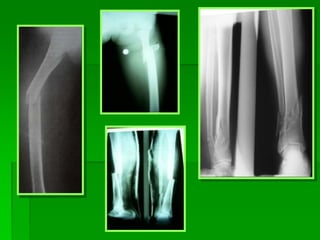

PIERNA – REV. ANATÓMICA

POYECCION AP DE PIERNA

 EL PACIENTE se coloca en posición supina,

con la pierna completamente extendida.

 LA PELICULA 35 X 43.

 EL CHASIS: longitudinal o diagonal.

 Colocar protección gonadal.

 EL RAYO: es perpendicular al plano, dirigido a

un punto medio de la pierna.

 ESTRUCTURAS MOSTRADAS: toda la tibia,

peroné, y las articulaciones de la rodilla y el

tobillo.

Lesiones de pierna

PROYECCION LATERAL – MEDIOLATERAL DE

PIERNA

 EL PACIENTE de cubito lateral, con el lado

afectado hacia abajo, la pierna contra lateral va

detrás del miembro afectado.